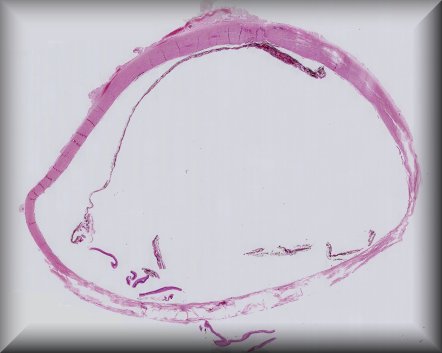

Tero Kivelä (Helsinki): A buphthalmic eye with congenital glaucoma, removed at debulking surgery for a progressive orbital neurofibroma in neurofibromatosis type 1, at the age of 3 1/2 years. Protocol |